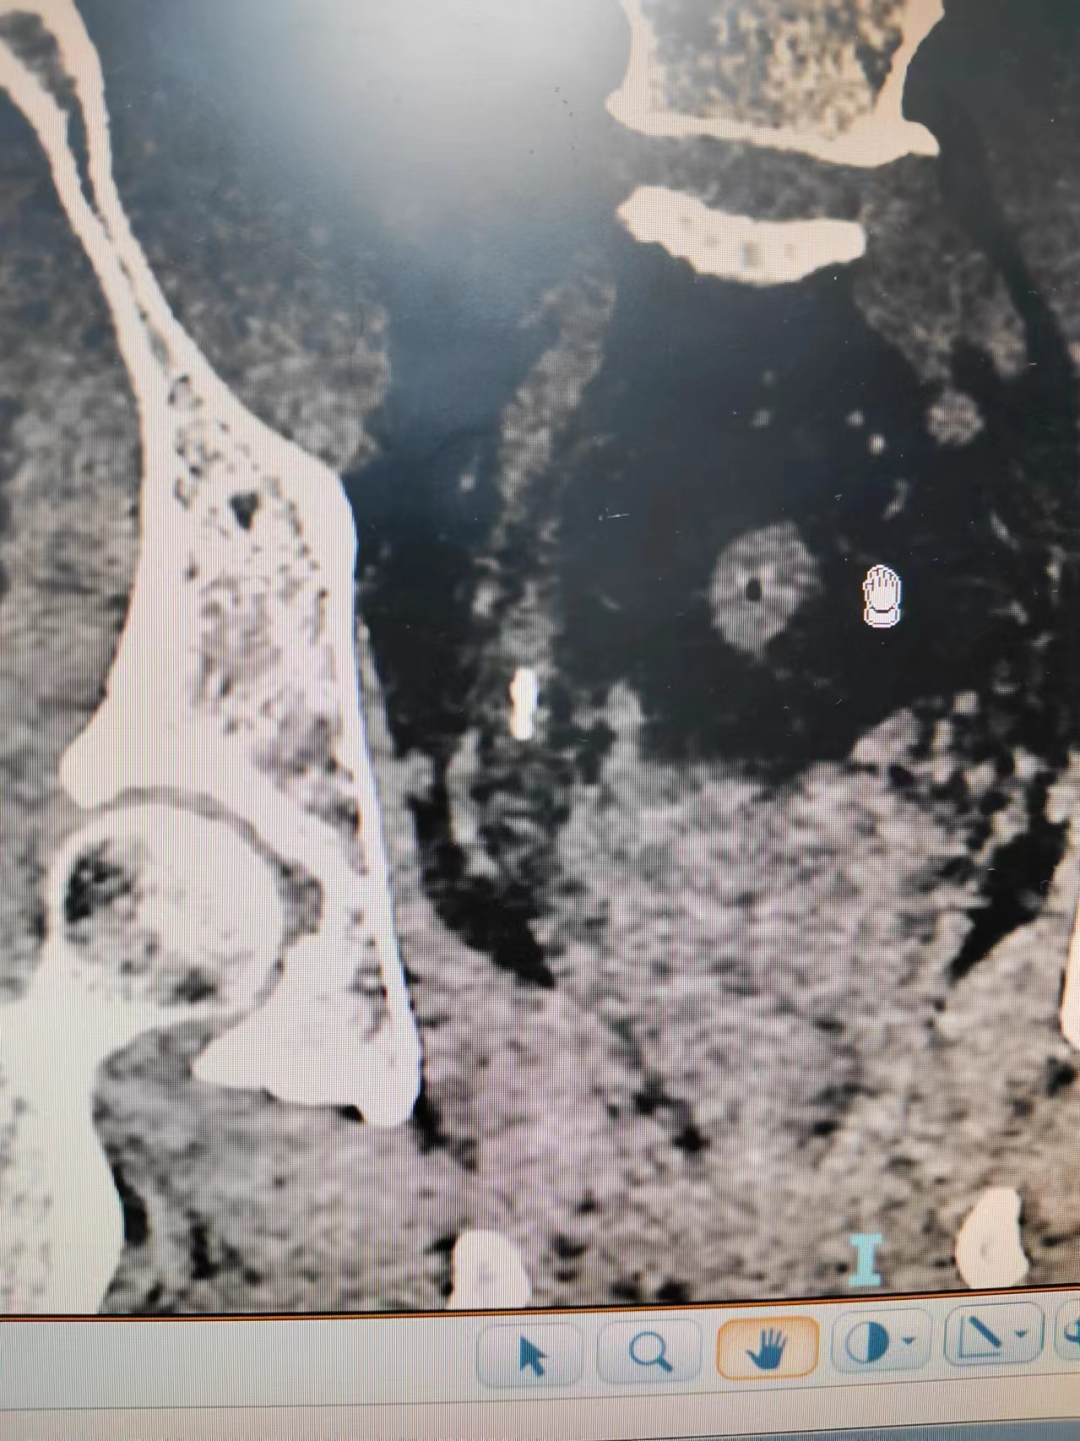

接診以后,立刻安排患者進行CT檢查,發現岳先生的結石是多個結石掉落在輸尿管內,形成“石街”。造成泌尿系統完全性梗阻,患者肌酐已經升高。